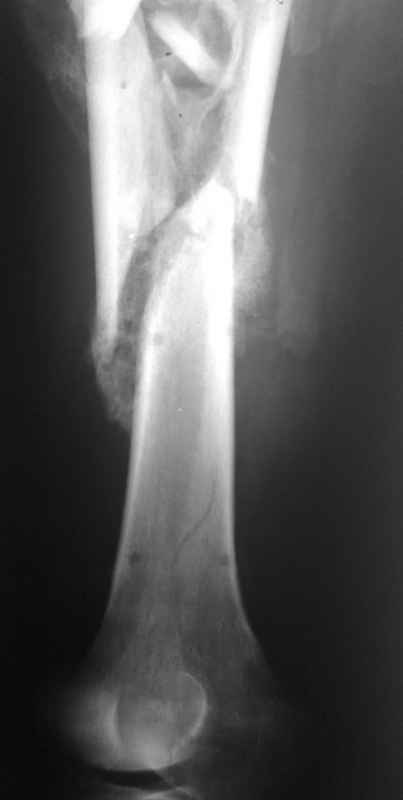

Пациент 39 лет. Травма в ДТП 2.5 месяца назад. Тяжелая сочетанная травма. ЗЧМТ. Тупая травма живота. Разрыв селезенки. Надрывы печени. Перелом бедра. При поступлении лапаротомия. Спленэктомия. Фиксация перелома бедра стержневым аппаратом. в последующем инфаркт мозга на фоне жировой эмболии. длительное нахождение на ИВЛ. Обширный пролежень в области крестца. и т.д.в настоящее время состояние больного стабилизировалось. активизирован на ходунках.имеется деформация бедра, укорочение 10 см. гранулирующий пролежень в области крестца. патологической подвижности в зоне перелома не отмечается.Оптимальные сроки проведения реконструктивной операции на бедре? Сейчас? Или после окончательного сращения?

А откуда такое укорочение взялось, 10см? По представленному фрагменту рентгенограммы понять трудно. В любом случае, если состояние пациента позволяет оперировать сейчас, зачем откладывать операцию до формирования монолитного сращения?

Конечно, снимки для планирования надо нормальные, не такой огрызок.

Спасибо за снимки. Предложения по тактике прежние.